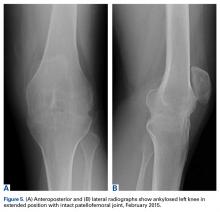

Magnetic resonance imaging showed soft-tissue swelling with knee joint chondrolysis (Figure 4). At the time, the working diagnosis was an inflammatory phenomenon, and the plan was to perform an arthroscopy and biopsies, but the patient did not follow-up.At the latest presentation (2015), the patient had a painless fixed extension deformity of the left knee joint and poor quality of life and wanted surgical intervention.

Plain radiographs showed extensive left knee joint destruction and fusion (Figures 5A, 5B).Discussion